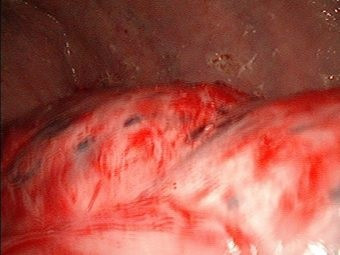

Decorticación pulmonar por paregonominiasis

Envíado por Dr. David Bará Egan